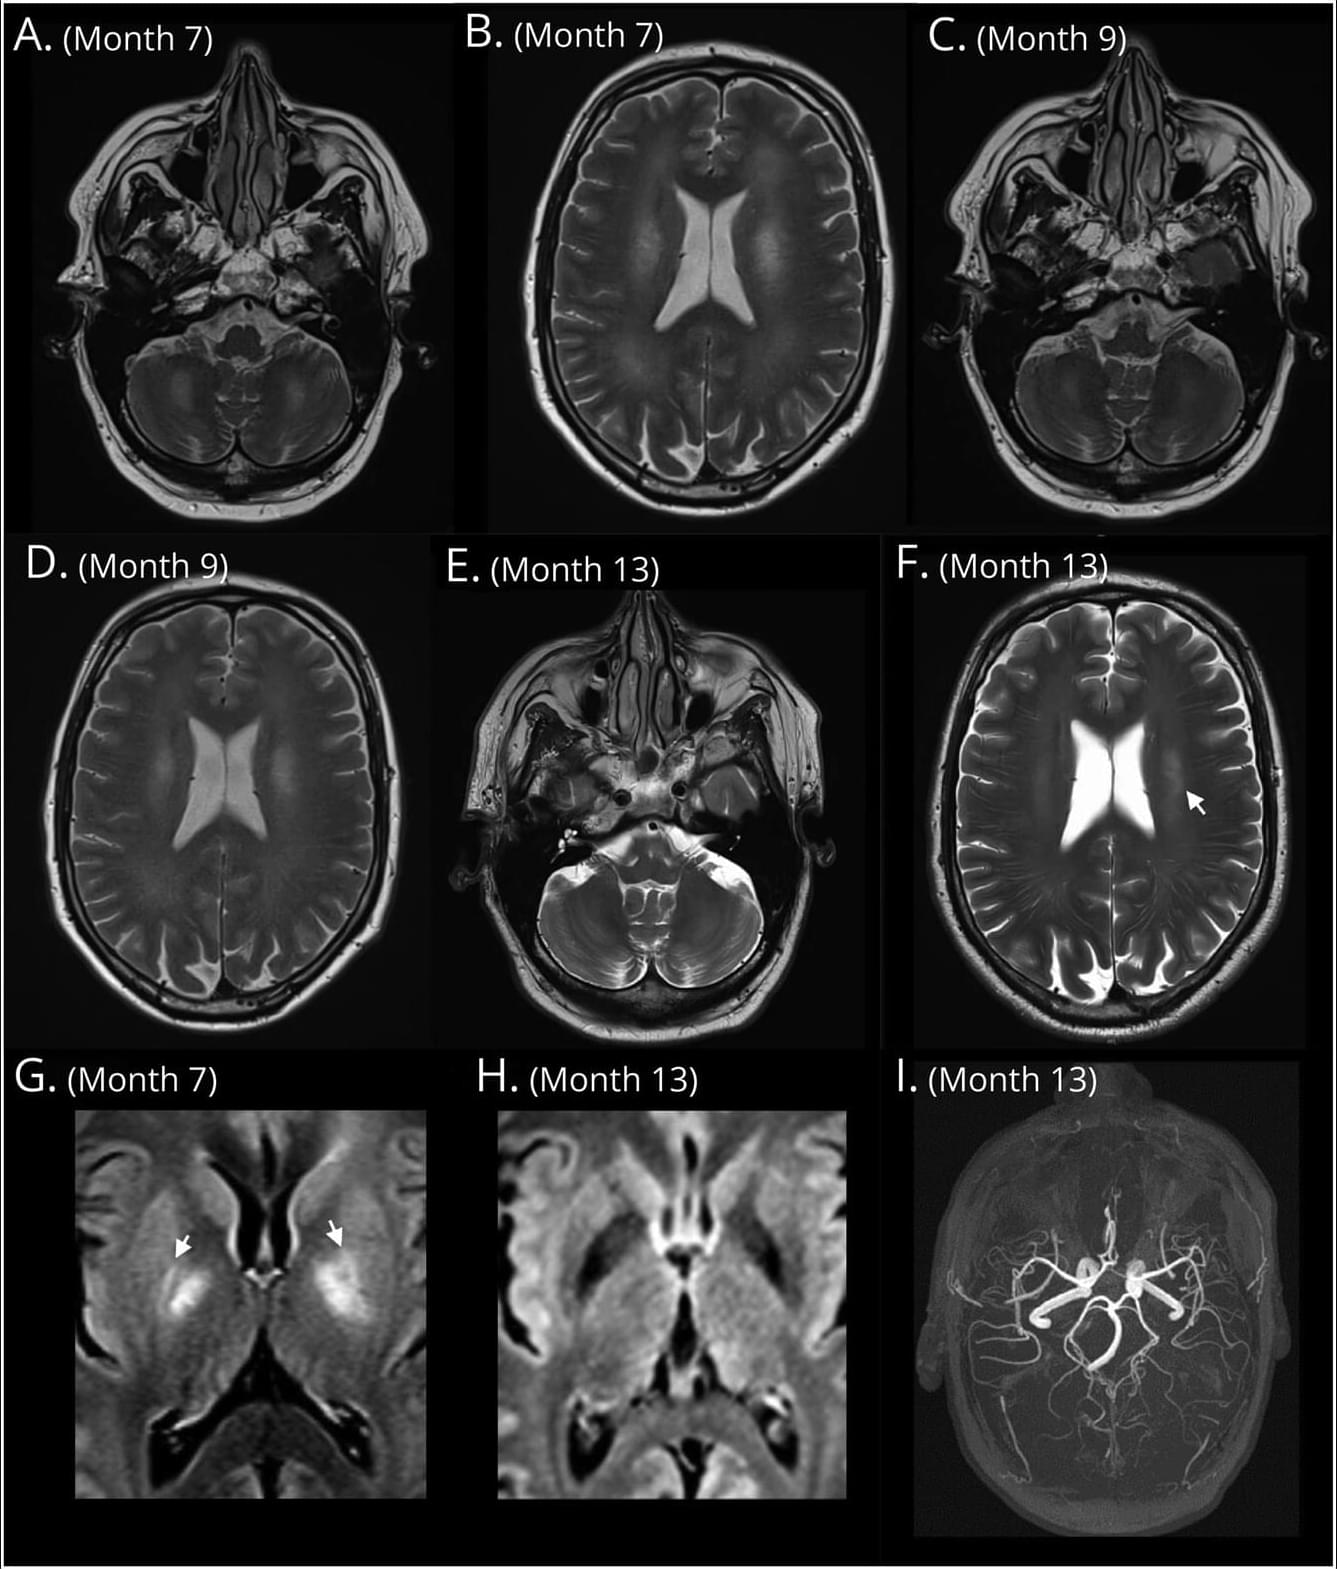

Both women with preeclampsia and gestational hypertension experience high blood pressure during pregnancy that frequently persists post partum.28 Lower white matter integrity has been reported from the peripartum period into later life.3,12,29 Hypertension-related white matter injury30,31 is associated with slower processing speed, executive dysfunction, and memory impairment.31 Although cognitive impact may not be obvious in the early postpartum period, white matter changes predict later cognitive decline and dementia,32 and converging longitudinal evidence suggests that reductions in white matter volume and integrity track cognitive decline, supporting the interpretation that better-preserved white matter is beneficial.33

Whether postpartum white matter changes are preventable or reversible had not been investigated. In this randomized clinical trial, a short-term blood pressure control intervention was associated with larger brain volumes several months later, when most participants were no longer taking antihypertensive medication. This is consistent with the postpartum period as a critical window for pregnancy-associated brain volume and blood pressure changes. Because baseline brain MRIs were not acquired, we cannot distinguish recovery of pregnancy-related changes from a slower postpregnancy decline relative to usual care.